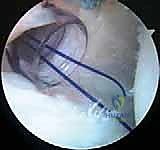

5. زرع الخطاطيف العظمية (Suture Anchors Insertion):

يتم زرع خطاطيف دقيقة جدًا (غالبًا ما تكون مصنوعة من مواد قابلة للامتصاص الحيوي أو مادة PEEK القوية) في حافة عظم التجويف الحقاني الخلفي. هذه الخطاطيف محملة بخيوط جراحية فائقة القوة.

6. خياطة الشفة وشد المحفظة (Capsulolabral Shift & Repair):

باستخدام أدوات تمرير الخيوط المتطورة، يقوم الدكتور هطيف بتمرير الخيوط عبر المحفظة المفصلية المرتخية والشفة الحقانية المتمزقة. يتم بعد ذلك سحب هذه الأنسجة وربط الخيوط بعقد جراحية محكمة.

هذه الخطوة المزدوجة تحقق هدفين: إعادة تثبيت الشفة في مكانها التشريحي الصحيح (بناء مصد خلفي يمنع خروج العظم)،